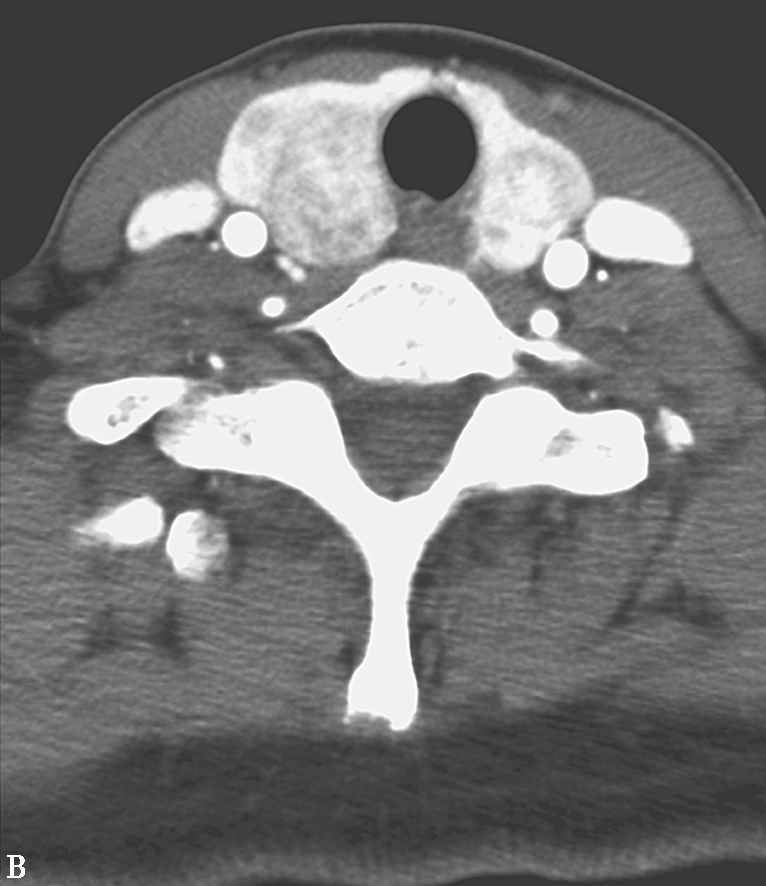

缺碘引起的弥漫性甲状腺肿大若未经及时治疗,病变发展可使扩张的滤泡集成多个大小不等的结节,逐渐形成结节性甲状腺肿。临床症状主要是肿大的结节增大后,压迫气管、食管和血管,引起呼吸困难、吞咽障碍和头面血液回流障碍的表现。CT和MRI检查都对结节性甲状腺肿大的诊断有重要价值,但相比而言,MR检查目前应用不如CT普及。CT平扫甲状腺弥漫性肿大,包膜完整,腺体表面隆起可呈浅分叶状。增大甲状腺可见多个大小不等低密度结节(图2-14A)。结节边缘可见弧样或粗斑点状钙化,增强扫描结节呈不同形式、不同程度的强化(图2-14B)。

图2-14 多结节性甲状腺肿

A.CT平扫横轴位;B.增强扫描,示双侧甲状腺增大,边缘规则,内可见多个散在的低密度结节,增强后结节呈不均匀强化